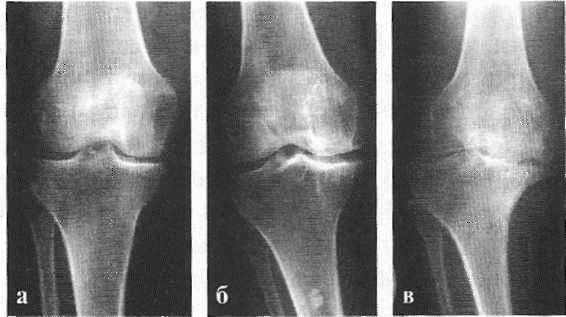

При оценке степени поражения коленных суставов и определения стадии деформирующего артроза использовали классификацию Келлгрена - Лоренса [92]:

0 - нет рентгенологических признаков остеоартрита (No radiographic findings of osteoarthritis);

1 - незначительные остеофиты сомнительного клинического значения (Minute osteophytes of doubtful clinical significance);

2 - выраженные остеофиты, суставная щель не изменена (Definite osteophytes with unimpaired joint space);

3 - выраженные остеофиты, умеренное сужение суставной щели (Definite osteophytes with oderate joint space narrowing);

4 - выраженные остеофиты, грубое сужение суставной щели и субхондральный склероз (Definite osteophytes with severe joint space narrowing and subchondral sclerosis).